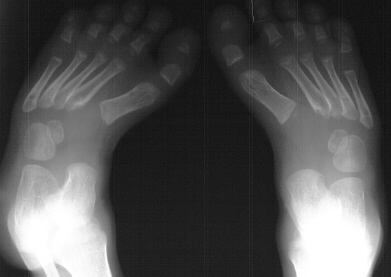

A 6 year old white male presents with a history of an undiagnosed

skeletal dysplasia. Previous surgery includes bilateral femoral

and tibial osteotomies for valgus deformities. His knee alignment

is now normal. His main complaint is the development of painful

callus over the arch of his foot and difficult in fitting shoes.

These deformities of the feet have been getting worse by the description

given by the mother. His foot deformity has never been treated

with casts or splints. On examination he has a short thick foot

with a kidney bean shaped curve to its lateral border. The arch

is not high but has a heavy callus bilaterally. The following

bilateral foot deformities were also present on physical examination:

hindfoot valgus of approx. 20-30 degrees, metatarsus adductus,

and prominence of the talar head in the medial arch with thickened

callus over the bony prominence.